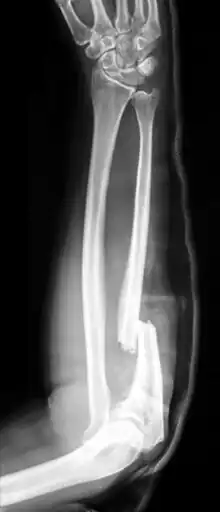

A fratura de Monteggia é uma fratura da ulna que afeta a articulação com o rádio. Mais precisamente, é uma fratura do terço proximal da ulna com deslocamento da cabeça do rádio.